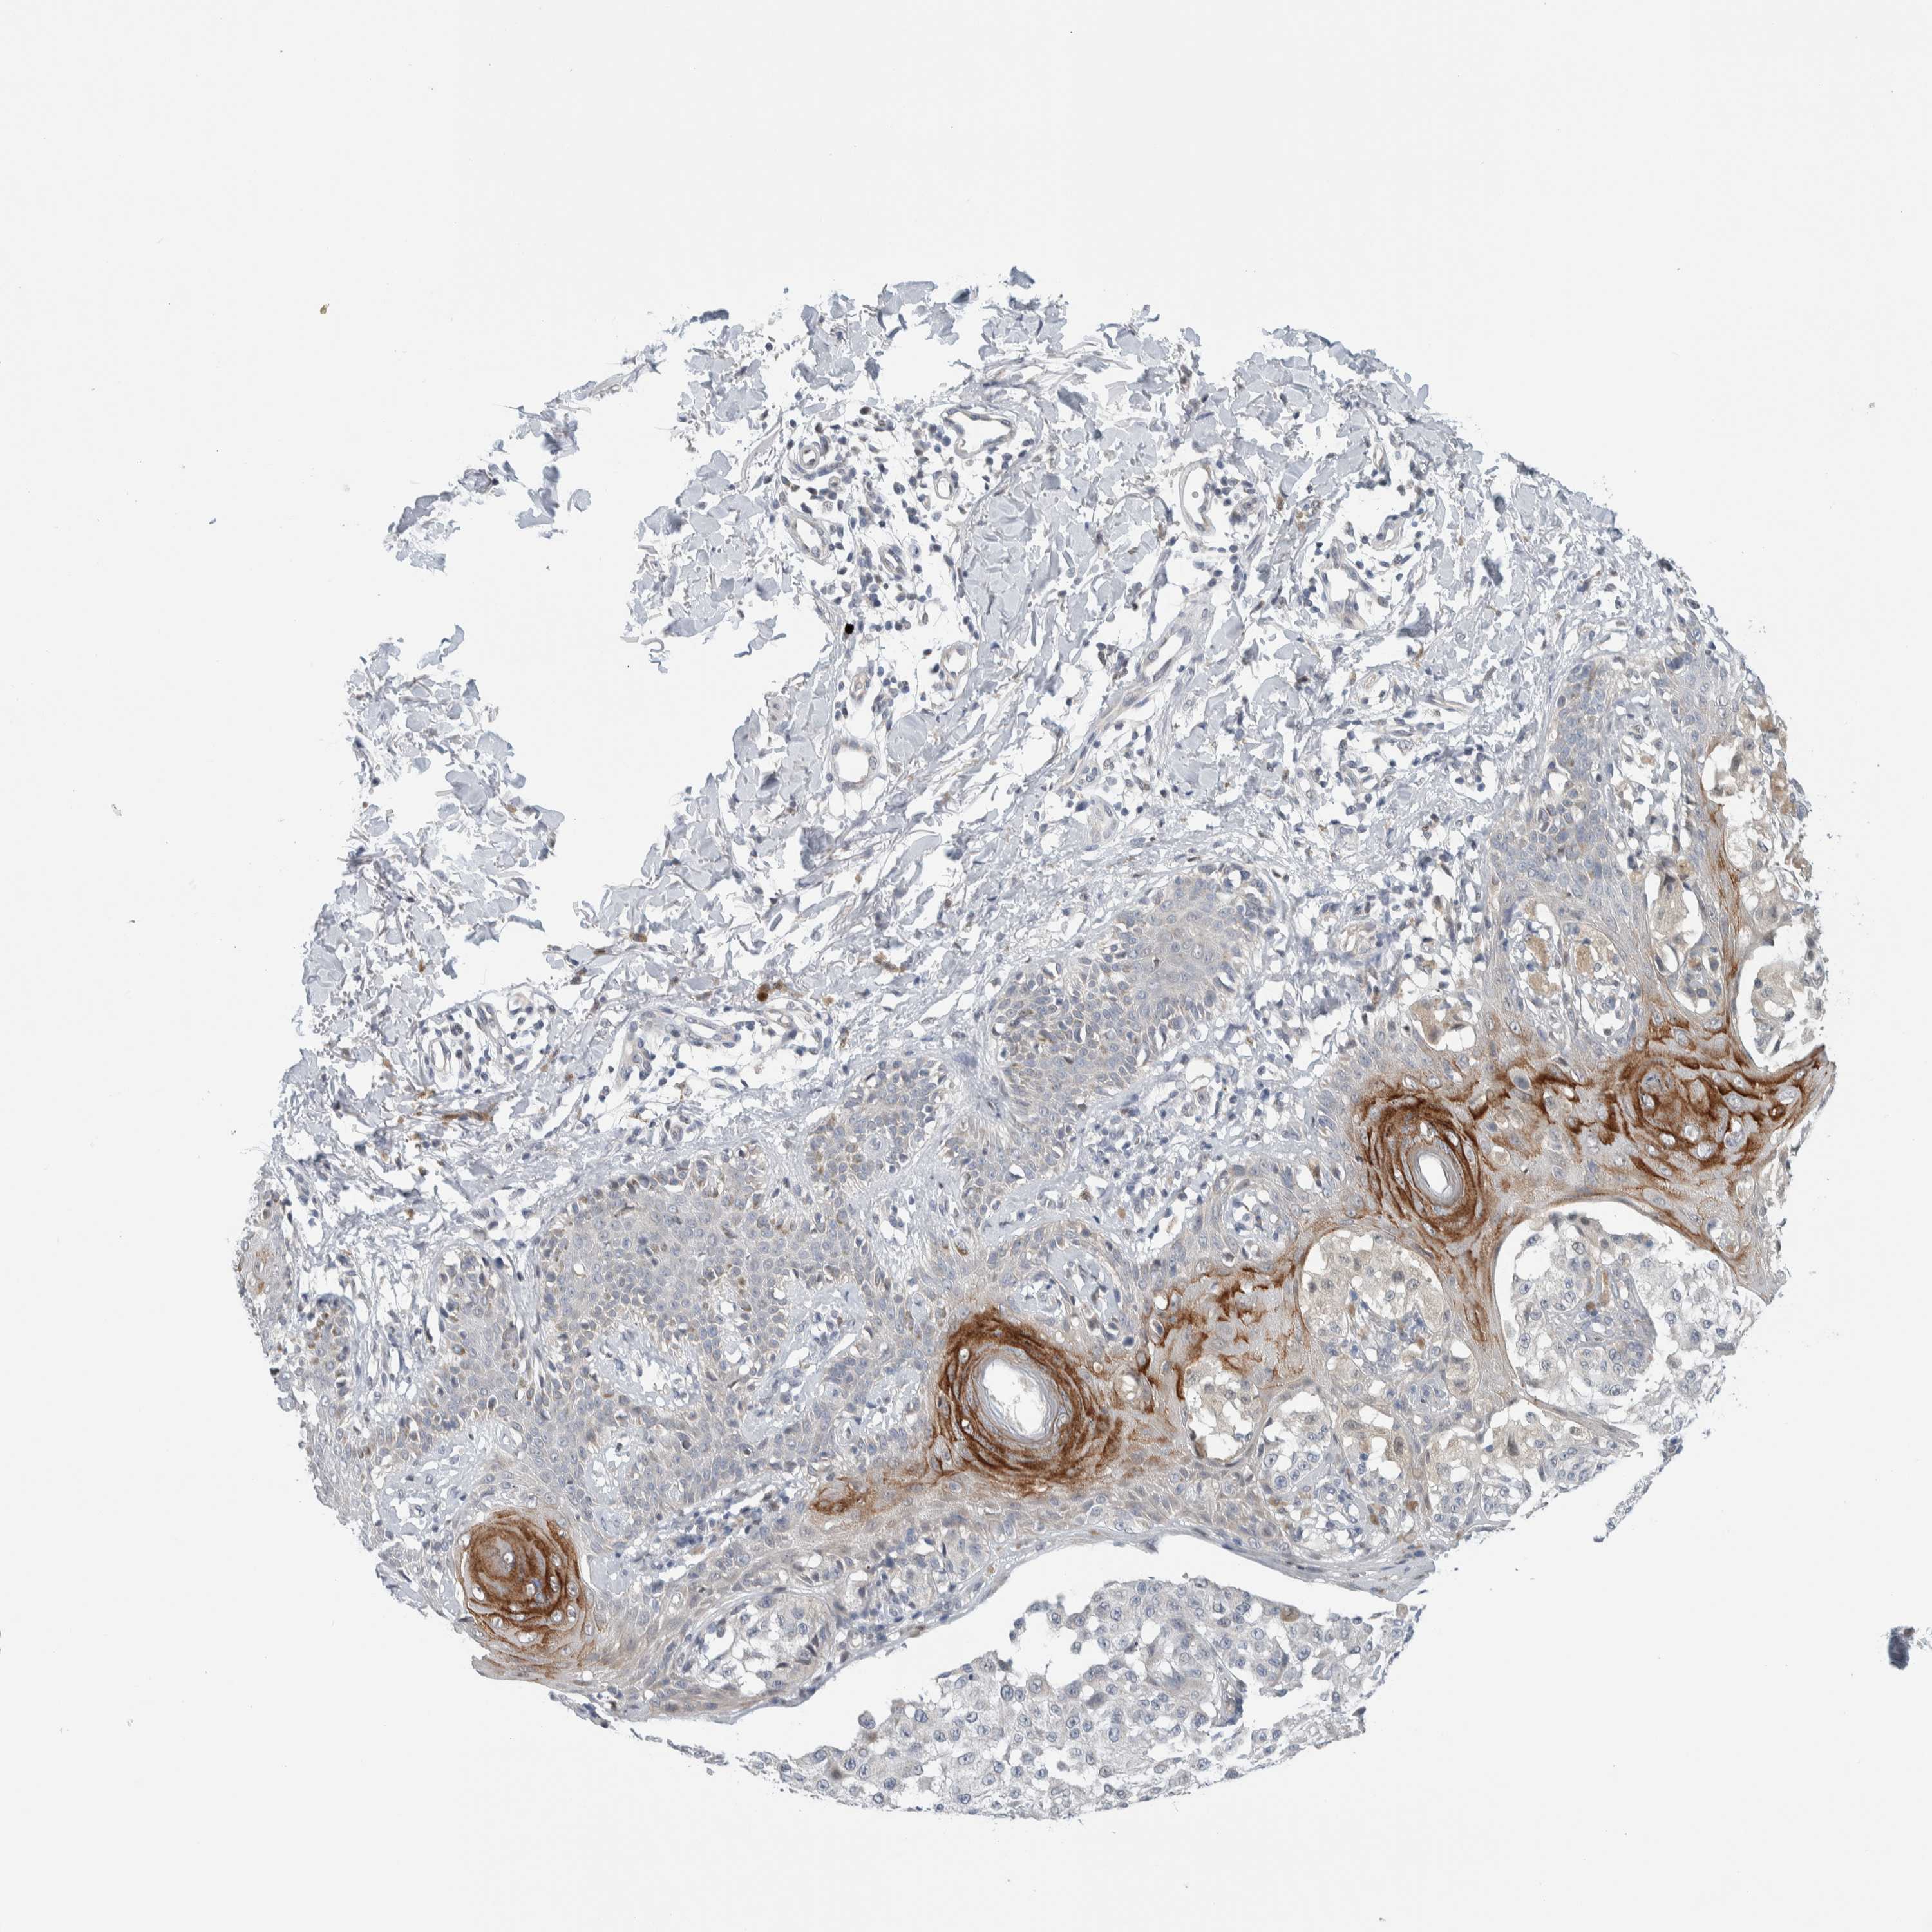

MELANOMA - Protein expressioni

A mouse-over function shows sample information and annotation data. Click on an image to view it in a full screen mode. Samples can be filtered based on level of antibody staining by selecting one or several of the following categories: high, medium, low and not detected. The assay and annotation is described here.

Note that samples used for immunohistochemistry by the Human Protein Atlas do not correspond to samples in the TCGA dataset.

Antibody stainingi

Antibody staining in the annotated cell types in the current human tissue is reported as not detected, low, medium, or high, based on conventional immunohistochemistry profiling in selected tissues. This score is based on the combination of the staining intensity and fraction of stained cells.

Each image is clickable and will lead to virtual microscopy that enables deeper exploration of all samples and also displays staining intensity scores, fraction scores and subcellular localization as well as patient and tissue information for each sample.

Antibody HPA003278

Antibody CAB022450

Staining

High

Medium

Low

Not detected

Intensity

Strong

Moderate

Weak

Negative

Quantity

>75%

75%-25%

<25%

None

Location

Nuclear

Cytoplasmic/membranous

Cytoplasmic/membranous,nuclear

Malignant melanoma, NOS

Malignant melanoma, Metastatic site